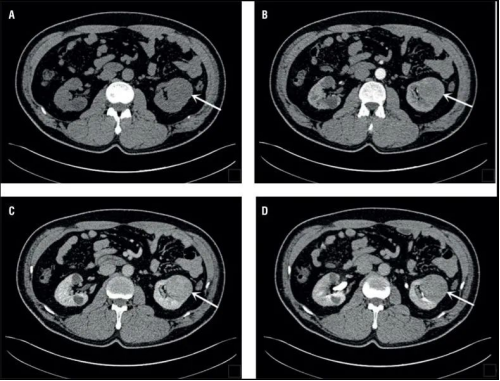

CT圖像舉例

CT

原理簡介:CT檢查相當(dāng)于把人體切成一定間距的小段,間距可以是0.25cm、0.5cm、1cm等等,切完以后可以在圖像上看到每一段橫切面的狀態(tài)。不同的切面呈現(xiàn)不一樣的臟器,通過掃描把人體各個部位的器官和結(jié)構(gòu)拉開,使我們可以看得非常清晰。

應(yīng)用:擅長神經(jīng)系統(tǒng)、心臟大血管疾病

優(yōu)點:可以斷層看,經(jīng)后期處理可以顯示更多信息;

缺點:輻射劑量高;